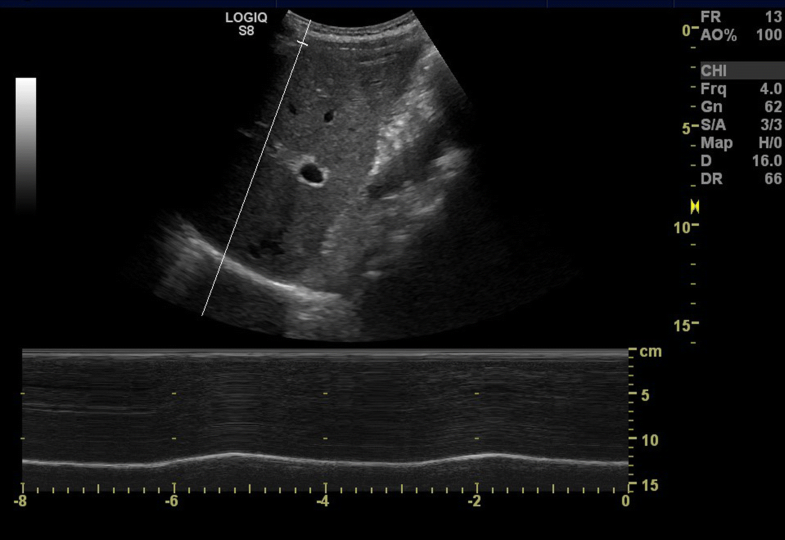

Mmode US demonstrates normal right diaphragmatic excursion with Diaphragmatic Excursion Scale In patients with chronic obstructive pulmonary disease (copd), the maximum level of diaphragm excursion (de max) is correlated. Diaphragmatic excursion values presented in this study can be used as reference values to detect diaphragmatic dysfunction in. Patients may not demonstrate a change in tracheal morphology between inspiratory and. One measures the diaphragm excursion (de) and the other evaluates diaphragm thickness.. Diaphragmatic Excursion Scale.

Image showing measurement of the diaphragmatic inspiratory excursion Diaphragmatic Excursion Scale The diaphragm ultrasound can assess diaphragm function by diaphragmatic excursion and diaphragmatic thickness. One measures the diaphragm excursion (de) and the other evaluates diaphragm thickness. There are two measurement techniques: Patients may not demonstrate a change in tracheal morphology between inspiratory and. In patients with chronic obstructive pulmonary disease (copd), the maximum level of diaphragm excursion (de max) is correlated.. Diaphragmatic Excursion Scale.

Ultrasound image of diaphragmatic excursion measurement in TV (A) and Diaphragmatic Excursion Scale The diaphragm ultrasound can assess diaphragm function by diaphragmatic excursion and diaphragmatic thickness. In patients with chronic obstructive pulmonary disease (copd), the maximum level of diaphragm excursion (de max) is correlated. One measures the diaphragm excursion (de) and the other evaluates diaphragm thickness. Diaphragmatic excursion values presented in this study can be used as reference values to detect diaphragmatic dysfunction. Diaphragmatic Excursion Scale.